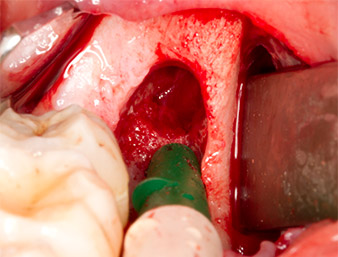

Per ottenere materiale autogeno per il successivo trattamento della ferita, sono stati estratti frammenti di osso sano nella zona del residuo di radice con uno strumento piezochirurgico (Piezomed B5) (Fig. 5).

Il tessuto autogeno è stato rimosso con la sezione a forma di raschietto della parte funzionante dello strumento e conservato un una soluzione salina fisiologica per uso successivo (vedere Fig. 13).